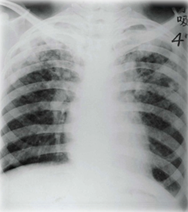

女,43岁。反复咳嗽咳脓痰10年,加重5天入院。吸烟史15年,已戒10年。查体:右下肺可闻及较多湿罗音及少量哮鸣音,可见杵状指。胸部X线片示右下肺纹理增粗、紊乱。应首先考虑的诊断

『答案解析』患者有反复的咳嗽、听诊下肺部有啰音、有杵状指等临床表现,结合胸片:肺纹理增粗,考虑符合支气管扩张。